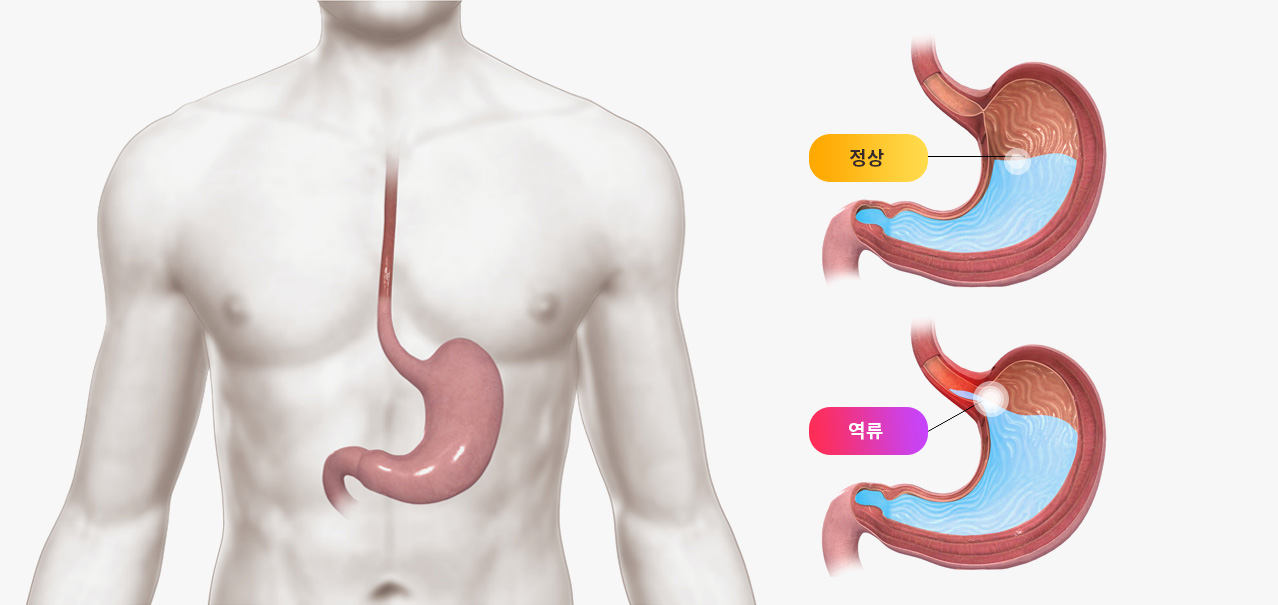

Background: The main symptoms of gastroesophageal reflux disease GERD are heartburn and acid regurgitation. Proton-pump inhibitors (PPI) are considered to be safe and effective for the treatment of GERD. In traditional Chinese medicine, wu chu yu tang (WCYT) is used to treat nausea after eating, vomiting, and diarrhea.

1966년 1월부터 2015년10월까지의 연구를 분석해보면 한약은 미란성-역류성식도염(GERD)과 비미란성-역류성식도염(NERD) 모두 치료효과를 보여주었는데 위장 장벽 기능 및 위 점액 개선, 위산 감소, 하부 식도 괄약근의 긴장 수축 유도 등의 메커니즘이 밝혀졌습니다.

중요한 것은 위 내시경 검사를 했을 때 이상이 없는 역류성식도염 환자, 즉 비미란성 - 역류성식도염(NERD)환자가 전체 역류성식도염 환자의 50~85%까지 차지한다는 것입니다.